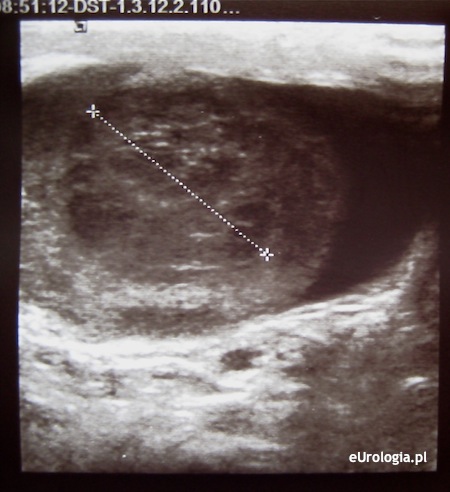

Fot. Guz dolnego bieguna prawego jądra - obraz USG